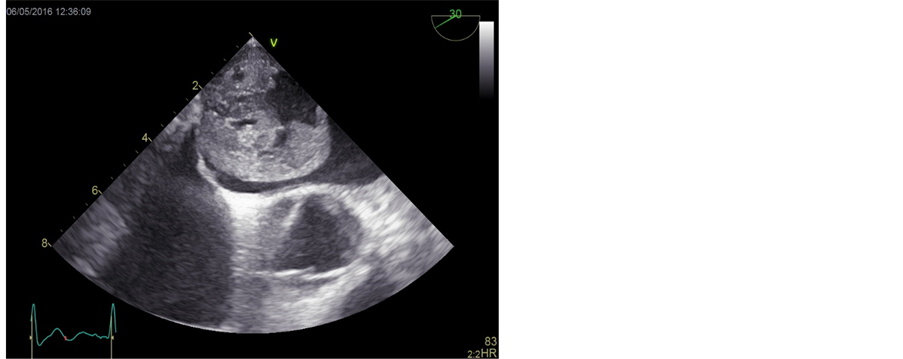

Transthoracic echocardiography revealed a tumour originating from the interatrial septum fossa ovalis in the left atrium (Figure 1). To determine the size and shape a CT-scan of the heart was conducted; the tumour measured 51 × 49 × 37 mm (Figure 2). Coronary angiography revealed abnormal arterial supply from RCA and CX to the tumour (Figure 3).

Figure 1. Transthoracic echocardiography showing a huge left atrialmyxoma. Left: two chambers view with the myxoma in left atrium, attached to the upper area of interatrial septum. Right: transoesophageal echocardiography with myxoma located in left atrium.